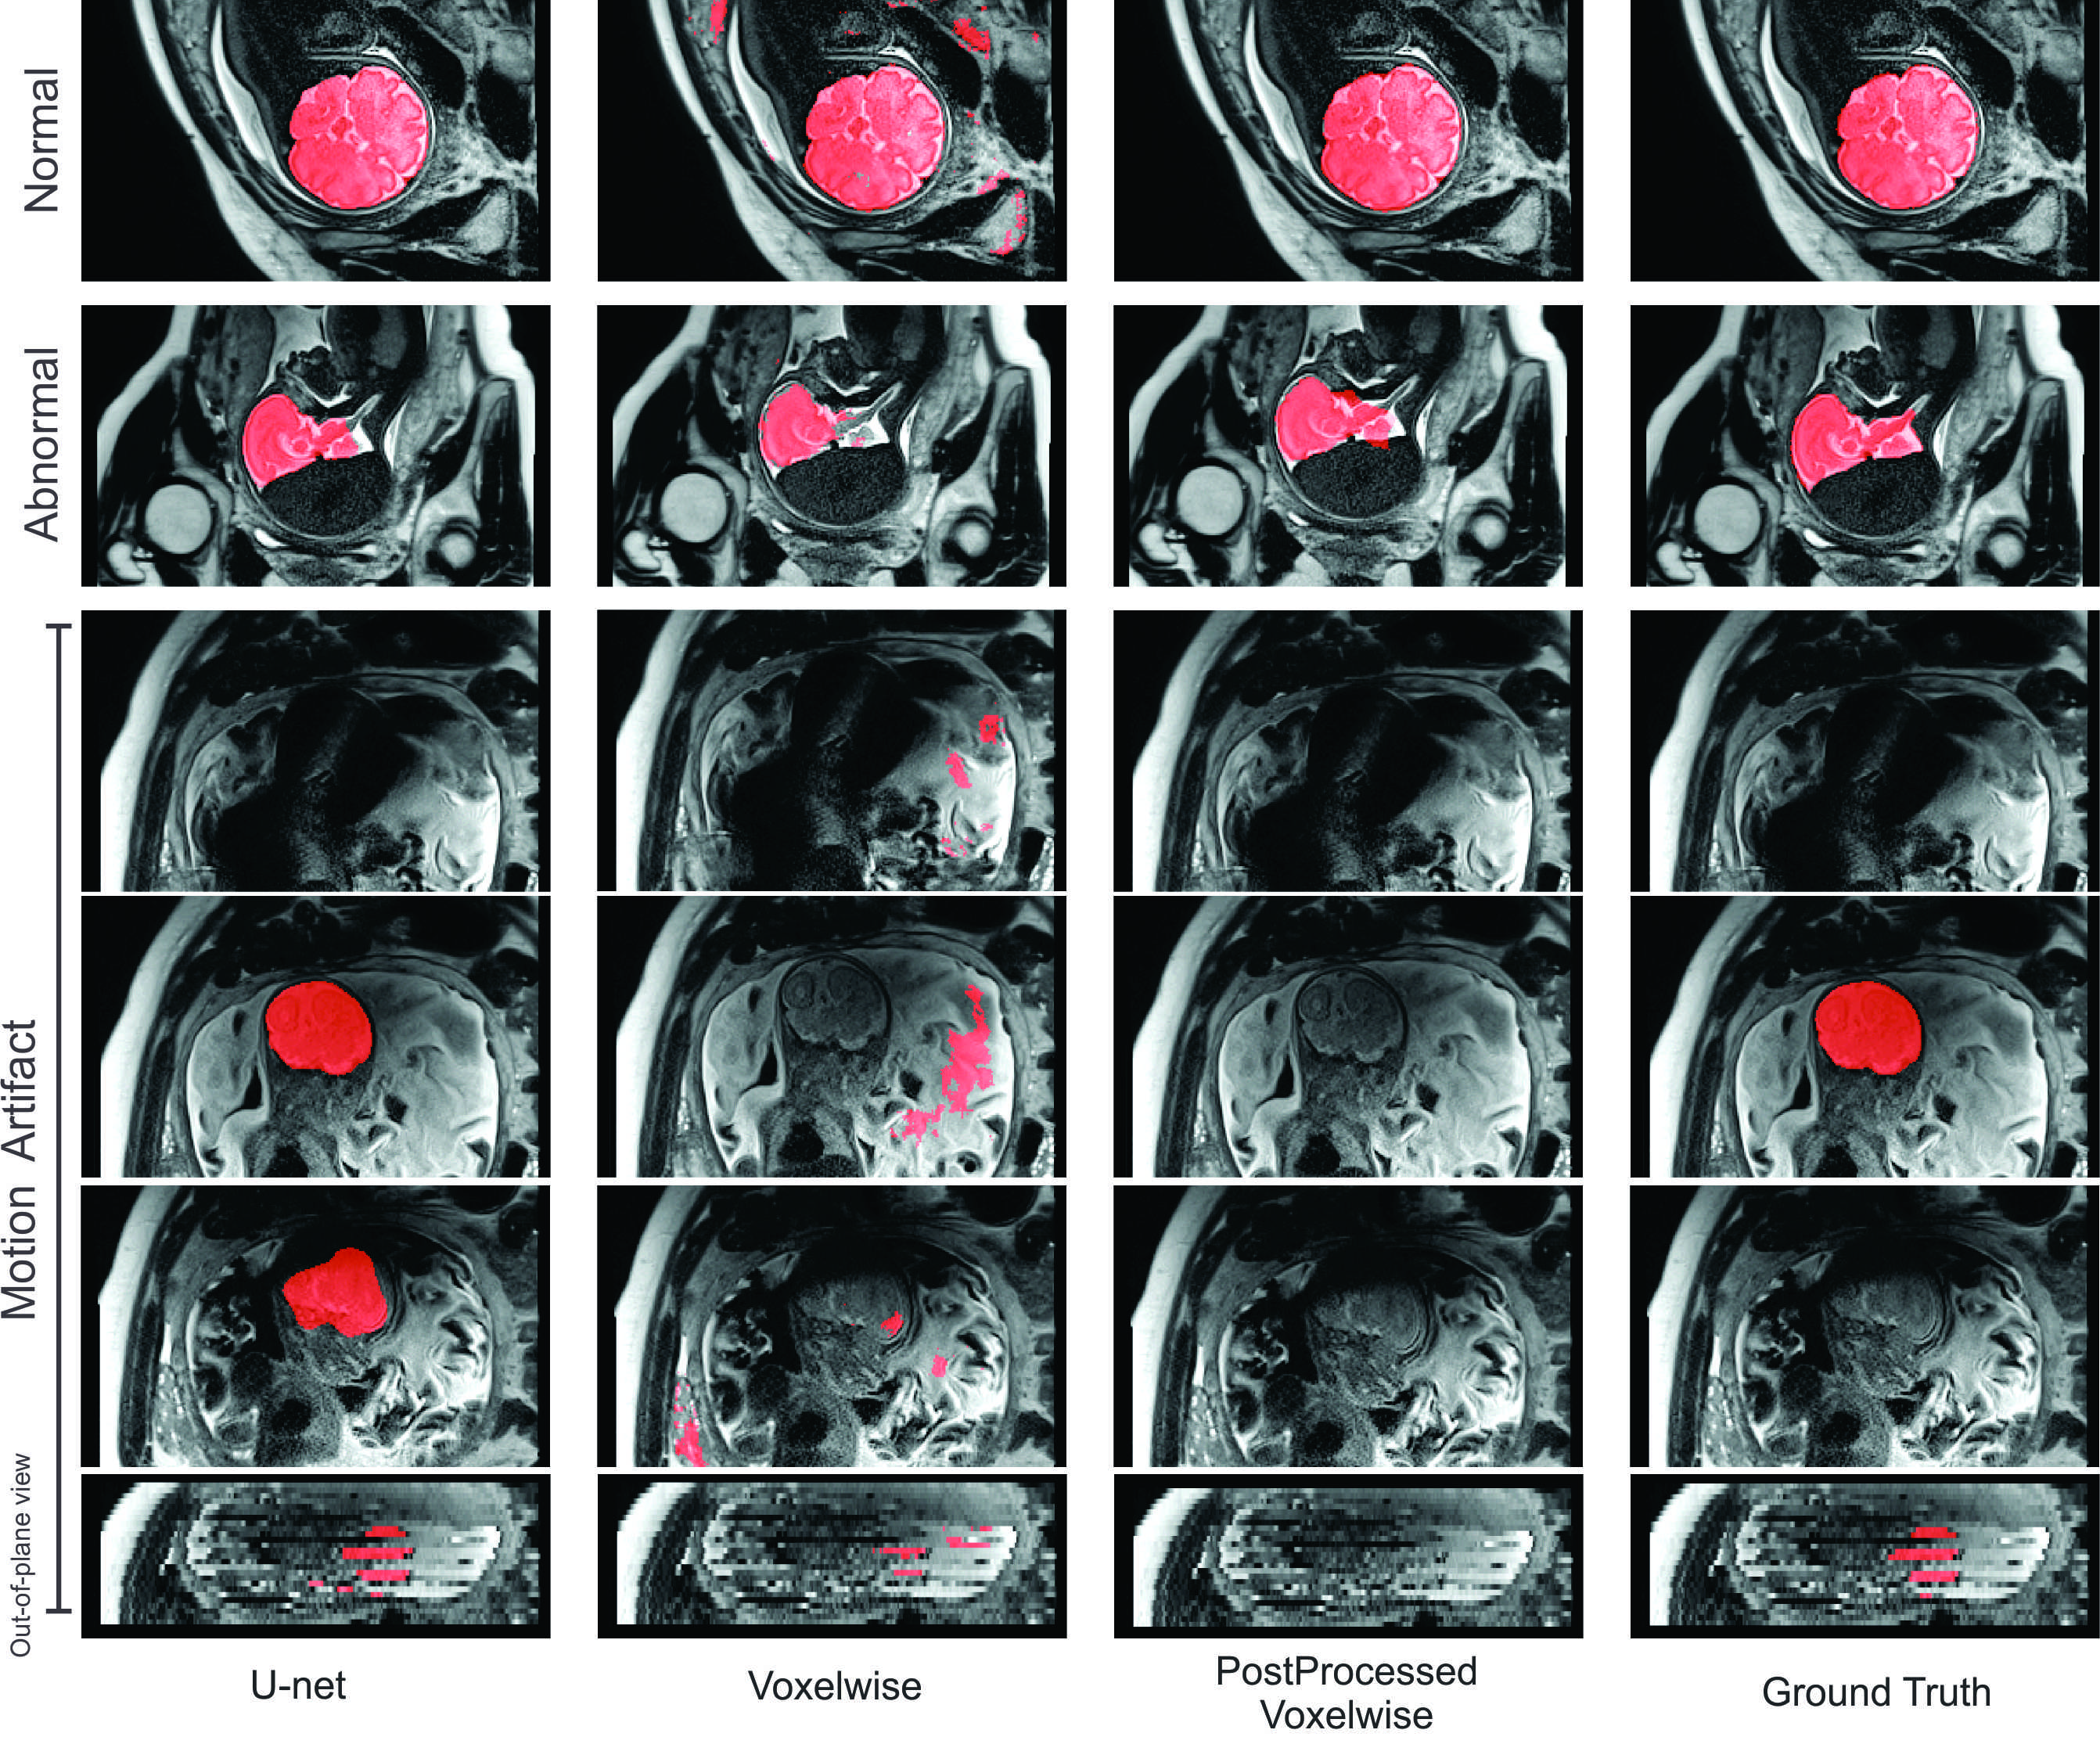

Fig. 2: Predicted brain masks overlaid on original fetal MRI for a normal case (top row), an abnormal case (second row), and a case with extreme motion (last four rows showing 3 consecutive slices and an out-of-plane view of the same stack); using U-net (first column), the voxelwise method (second column), voxelwise after post processing (third column), and the manually drawn ground truth (last column). The U-net approach performed much better than the voxelwise method. Note that U-net detected part of the brain in a motion-corrupted scan which was not segmented by the expert due to perceived motion corruption.

Figure 1 shows boxplots of Dice, sensitivity and specificity of all the analyzed methods for normal and challenging test datasets. In Figure 2, we demonstrate slices of the results of the U-net and voxelwise methods for three cases: a case from the normal test set; a case with severe brain abnormality; and three adjacent slices of a case with extreme motion as well as an out-of-plane view of these images. Although there are lots of inter-slice motion, the U-net based method was capable of segmenting the brain quite accurately. The upsampling layers and concatenations in U-net helped effectively learning multi-scale information on 2D slices. Overall, both quantitative and qualitative evaluation results indicate that U-net performed significantly better than the 3-pathway voxelwise method in brain segmentation. We note that the bSIFT-RF-CRF method failed in 11 out of 18 challenging test stacks in the brain detection step presumably due to the failure of a RANSAC process to reject the influence of outliers. These cases with severely abnormal brain shape and extreme motion pose challenges for such statistically-driven methods.